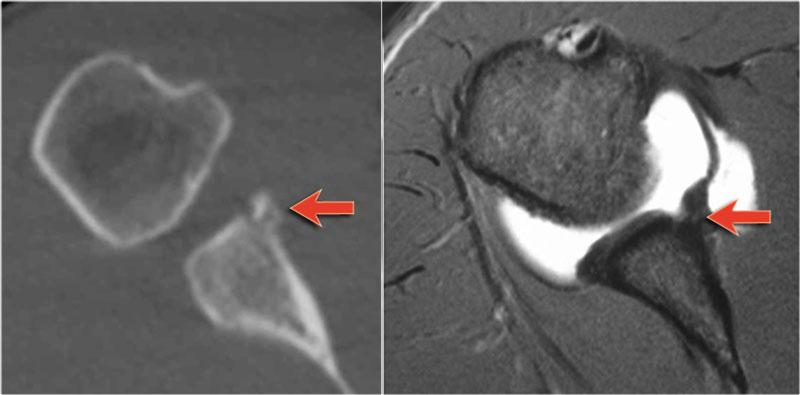

Tổn thương Bankart kèm mảnh xương là phát hiện thường gặp ở bệnh nhân trật khớp ra trước và thường được nhìn thấy trên X-quang hoặc CT.

Trên MRI khớp cản từ, việc xác định mảnh xương có thể gặp khó khăn.

Trên CT, mảnh xương ở phía trước ổ chảo dễ dàng được nhận diện (mũi tên).

Cuộn qua các hình ảnh.

Có tổn thương Bankart xương (mũi tên đỏ cong).

Đường rách lan lên trên (mũi tên đen).

Ngoài ra còn có khuyết Hill-Sachs (mũi tên đỏ).

Hình MRI khớp cản từ mặt phẳng đứng dọc cho thấy sự lan rộng lên trên của đường rách Bankart.